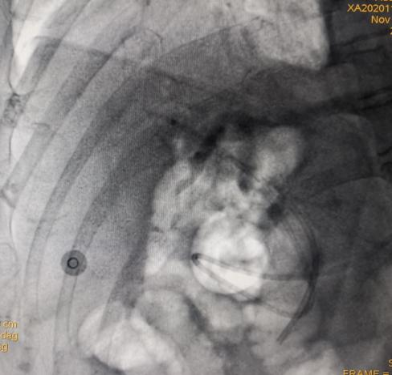

(胆管插管成功,导丝进入胆管内) (胆管支架植入,解除胆道梗阻和胆道高压)

凭借扎实的ERCP专业功底和内镜操作技能,ERCP团队在短短20分钟就顺利完成了ERCP+EST+取石+ERBD+ENBD术,即胆总管造影、十二指肠乳头切开、胆总管末段嵌顿结石取出、胆总管支架植及鼻胆管引流术系列手术操作。

(ERCP术后胆管支架、鼻胆管X光线图片)